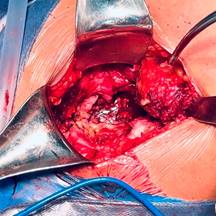

Con la paciente bajo anestesia regional y previa profilaxis antibiótica, se coloca en posición de cubito lateral derecho. Por anatomía de superficie se identifican referencias anatómicas: trocánter mayor y diáfisis femoral. Se realiza un abordaje lateral directo de Hardinge, disección por planos aplicando hemostasia con electrocauterio, se hace un corte longitudinal de fascia lata con tijera de Metzenbaum; se efectúa colgajo muscular de glúteo medio y menor (Figura 2); posterior a esto, capsulotomía en T invertida, para identificar cabeza femoral y realizar osteotomía a 10 mm por arriba del trocánter menor; se identifica ligamento redondo (Figura 3), con el fin de diseccionar hasta su origen sobre la escotadura y localizar el acetábulo nativo, retirando tejido blando remanente de cápsula articular (Figura 4).